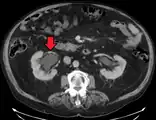

CT scan of bilateral hydronephrosis due to a bladder cancer

Massive hydronephrosis as marked by the arrow- Renal ultrasonography of hydronephrosis[16]

- Stone causing hydronephrosis[16]